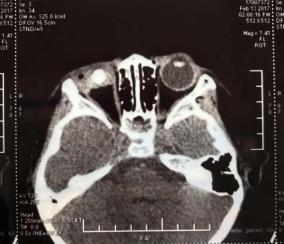

病情嚴重到必須立即給博博安排急癥手術,否則就會導致眼球萎縮,眼內感染等嚴重后果。3歲的男孩對手術是充滿恐懼的,不停地問,做手術疼不疼?在手術室對醫生說:“能等我睡著了再給我做手術嗎?”醫生答應了他,在全麻下輕輕打開他的眼瞼,一點一點地清理孩子的傷口,孩子的角膜上有一處幾乎縱貫全角膜的Y字型裂傷,眼內容物幾乎全部脫失,視力預后將會非常的差,看到這一幕,手術醫生原公強主任心情非常的沉重。

時間不知不覺的就來到了凌晨,原公強主任從孩子的眼睛中取出長約15mm,直徑約4mm的石質異物,并進行了角、鞏膜裂傷縫合術,經過3個小時手術,終于保住了孩子的眼睛。醫生從孩子眼球中取出的異物讓所有的人都感到觸目驚心。?